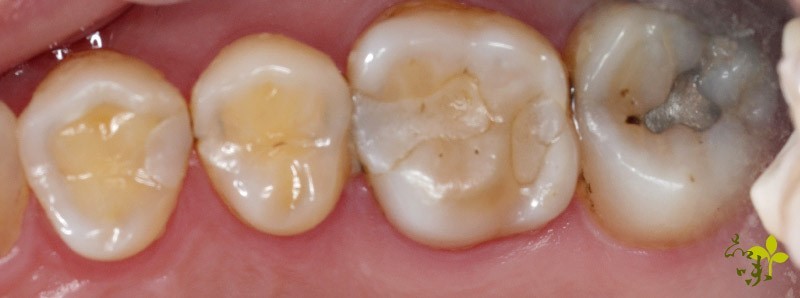

病人牙齒鄰接面有多顆蛀牙,合併有齒裂細紋,建議用微創齒雕(陶瓷嵌體)復形。圖/黃文龍醫師 @ 新竹品味牙醫

修復過程。圖/圖/黃文龍醫師 @ 新竹品味牙醫